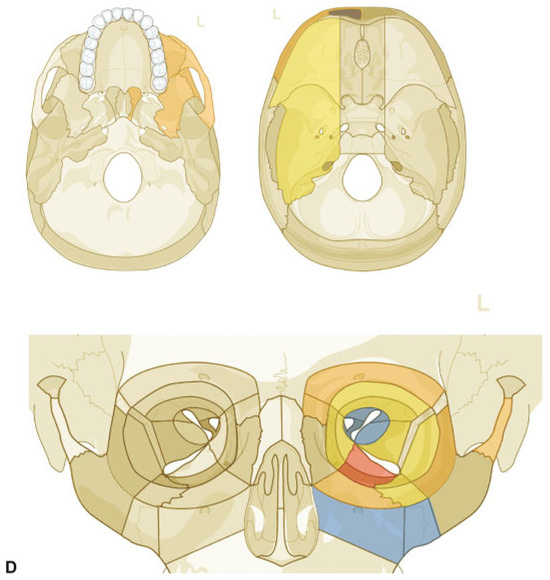

Figure 6.

Asymmetric Le Fort Level midface fracture. Three-dimensional (3D) computed tomographic (CT) scans— (A) frontal view, (B) lateral view right, (C) lateral view left, (D) basal view—mandible removed; (E) panoramic X-ray–OPT; (F, G) 3D CT scans—oblique views, right,left (H, I) coronal CT scans. (J–M) axial CT scans; (N) sagittal CT scans—at lateral lamina of pterygoid process right, (O) at medial lamina of pterygoid process right, (P) at medial lamina of pterygoid process left, (Q) at lateral lamina of pterygoid process left, and (R) at lateral orbital rim left. (S) Level 3 Code : 92 I0i.L0.Pt0.Oim.U1m.Omil.Pt0.L0.Z0, Orbit (right): R(im).W1(im)2(i), Orbit (left): R(lm).W1(lim)2(i), This case example CMTR-92-101 is made available electronically for viewing using the AOCOIAC software at www.aocmf.org/classification. Narrative description: Le Fort analogous midface fracture (central right—types I and II/centrolateral left types I and III). Unilateral NOE fracture right—large fragments, multifragmentation of facial antral wall right, nasal skeletal fracture (multifragmanted and displaced) involving both frontonasal processes and nasal bones not reaching cranially to the nasofrontal suture. Partial Dentition (FDI): Lack of 18–14; 24–28. Maxillary alveolar process atrophy: moderate. Pterygoids: bilateral incomplete horizontal fractures, no pterygomaxillary disjunction, i.e., vertical separation. Displacement: No retrodisplacement of both maxillae, no displacement of the Le Fort I and III fragments left, multifragmentation facial antral wall right, minor displacement of frontonasal fragment right. Internal orbits: Involvement confined to anterior and midorbit sections: right, medial and inferior walls, left medial, inferior and lateral walls.